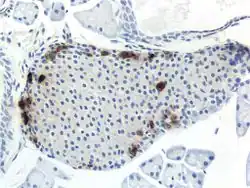

![]() b: Hetzelfde PP-celrijke gebied geprojecteerd op de alvleesklier in een anatomische positie (in vivo). |

Door middel van verschillende microscopietechnieken zijn de structurele details van PP-cellen beter begrepen. Dit omvat hun grootte, hoe hun celmembranen eruitzien, de eiwitten die ermee verbonden zijn en zelfs hun afmetingen. PP-cellen zijn langwerpige cellen. Een ander detail is te zien in insuline-secretiekorrels, of containerachtige knoppen, die insuline in een cel opslaan. In PP-cellen zijn de insulinekorrels kleiner en bolvormig en vergelijkbaar met die in alfacellen. Dit is ook te zien in menselijke PP-cellen, maar er is aangetoond dat verschillende dieren korrels hebben van verschillende groottes vergeleken met mensen, zoals knaagdieren. Bij katten en honden hebben PP-cellen grote korrels.[8] Bij ratten hebben PP-cellen weinig korrels, net als bij mensen. Bij honden bevinden sommige PP-cellen zich in de wanden van het antrum van de maag.[4]